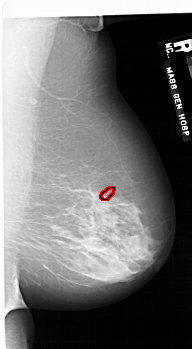

A_1749_1.RIGHT_CC

RIGHT_CC LINES 6856 PIXELS_PER_LINE 3751 BITS_PER_PIXEL 12 RESOLUTION 43.5 OVERLAY

FILE: A_1749_1.RIGHT_CC.OVERLAY

TOTAL_ABNORMALITIES 1

ABNORMALITY 1

LESION_TYPE CALCIFICATION TYPE PLEOMORPHIC DISTRIBUTION CLUSTERED

ASSESSMENT 4

SUBTLETY 4

PATHOLOGY BENIGN

TOTAL_OUTLINES 1

BOUNDARY